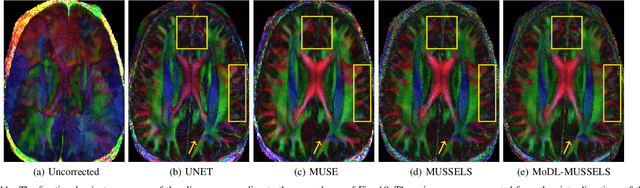

Abstract:We propose a model-based deep learning architecture for the correction of phase errors in multishot diffusion-weighted echo-planar MRI images. This work is a generalization of MUSSELS, which is a structured low-rank algorithm. We show that an iterative reweighted least-squares implementation of MUSSELS resembles the model-based deep learning (MoDL) framework. We propose to replace the self-learned linear filter bank in MUSSELS with a convolutional neural network, whose parameters are learned from exemplary data. The proposed algorithm reduces the computational complexity of MUSSELS by several orders of magnitude while providing comparable image quality.